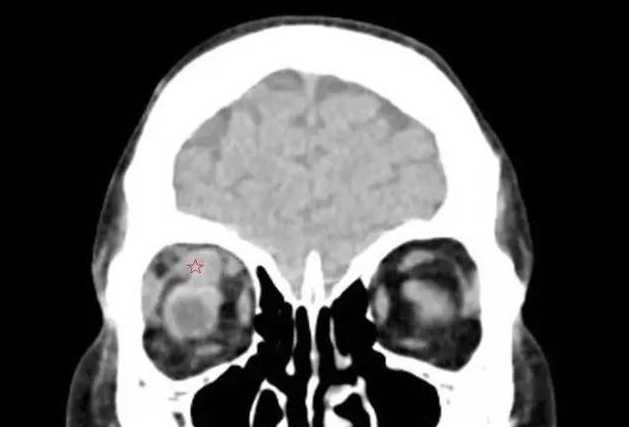

来自泉州南安的刘先生发现自己的眼睛莫名的越来越突,还容易流眼泪,转动不灵活,看东西模糊,一个东西变成两个,看马路上的车一辆变成两辆,上下楼梯也踩不准,并且脾气变得暴躁。在当地医生的建议下,今年4月,刘先生又来到了厦门眼科中心斜视与小儿眼科检查,谢仁艺副主任医师在询问了解了刘先生的病情后,并结合各项检查报告判定刘先生是患了甲状腺相关眼病。

谢仁艺副主任医师介绍,刘先生眼睛病变是因甲亢引起,导致双眼眼外肌发炎、肿胀、变性、纤维化, 终失去弹性,这也是他眼球转动不灵活引起斜视、复视的主要原因。